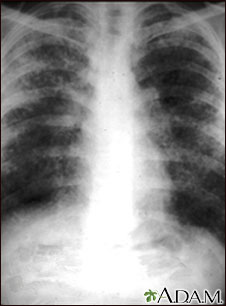

Sarcoidosis, estado II - radiografía de tórax

La sarcoidosis causa daños en el tejido pulmonar que pueden sanar con la cicatrización. Esta diapositiva muestra el área pulmonar, normalmente de apariencia oscura, con un aspecto lechoso y granuloso. Este individuo sufre una grave disminución de la función pulmonar.